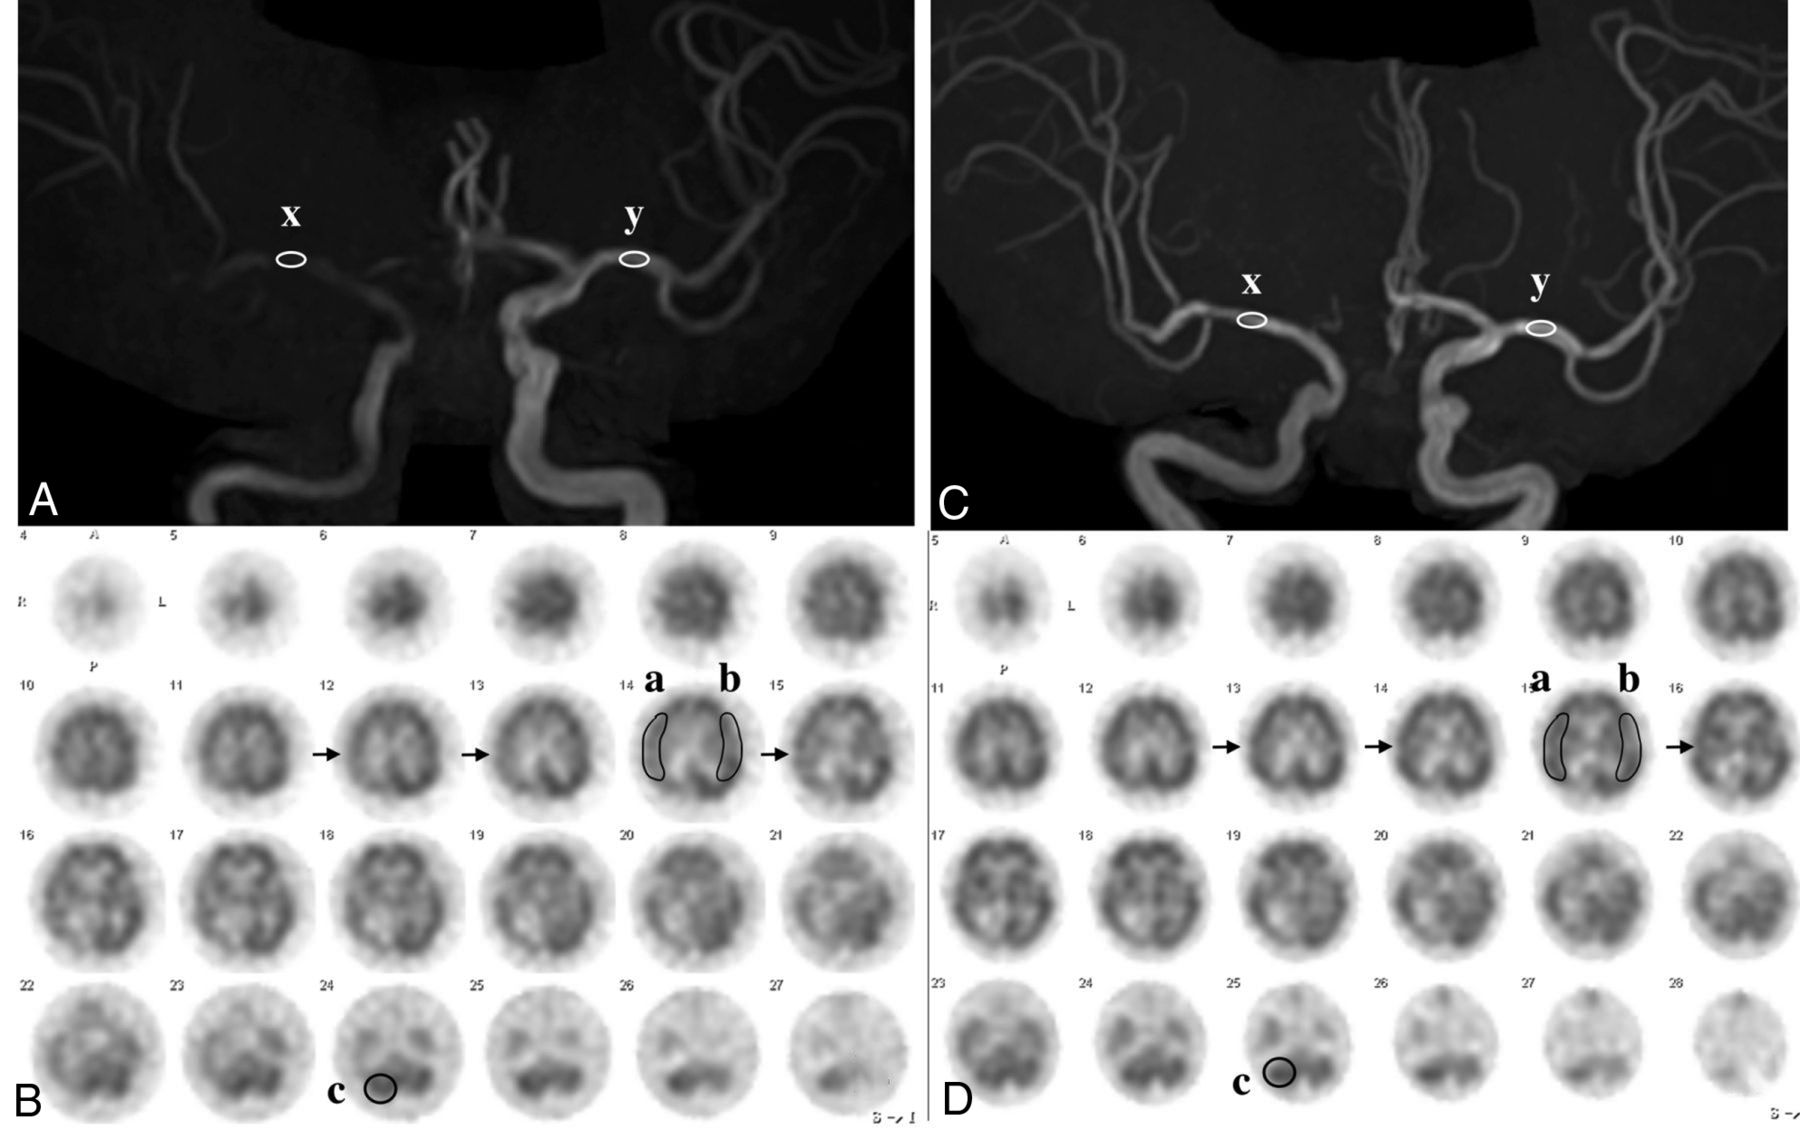

MRA and SPECT in the same case as in Fig 1. A, MRA before CAS reveals an MCA rSI value of 0.44: [(x: 784) divided by (y: 1775)]. B, SPECT before CAS demonstrates a CBF decrease in the right MCA territory (arrows). AI was 80.3%% [(a: 31.94) divided by (b: 39.78)], and rCBF% was 83.9% [(a: 31.94) divided by (c: 38.07)]. C, MRA after CAS reveals an MCA rSI of 1.16: [(x: 2967) divided by (y: 2667)]. D, SPECT after CAS demonstrates a CBF increase in the right MCA territory (arrows). AI% was 92.7% [(a: 37.95) divided by (b: 40.93)] and rCBF% was 99.9% [(a: 37.95) divided by (c: 37.99)]. rSI indicates relative signal intensity.

Nine patients (32.1%) with hyperintensity on T1-weighted black-blood MR imaging underwent balloon predilation with a semicompliant 3.0-mm balloon catheter. The median NASCET% decreased after CAS (P < .001). The median MLD values before and after CAS were 0.63 and 2.9 mm, respectively (P < .001). Gentle CAS successfully provided intentional residual stent stenosis (Fig 1). The MCA relative SI increased after CAS (P < .001), and the PSV decreased after CAS (P < .001). The AI% and rCBF% increased after CAS (P < .001). The AVDO2 decreased (P = .02), and the OEF remained unchanged after CAS (Table). The HI criteria successfully identified patients with HI.